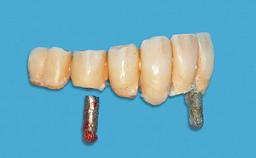

An 83-year-old man presented together with his caregiver at the dental department of the Medical University of Innsbruck, Austria with complaints of swelling in the right maxillary canine area and loss of retention of his 5-years-old mandibular denture. The patient had a significant medical history (20 years) of bipolar affective disorder with moderate depression (F 31.3) and dementia in Alzheimer’s disease (F 00.2). The patient had been in ambulant psychiatric therapy for his depressive illness for the past 20 years. He lived alone and had no children; his sister assisted with daily living. She reported that the patient exhibited compulsive hoarding behavior. In the previous two months, she had noted increasing disorientation and vertigo in the patient. She therefore accompanied him for a medical consultation at the Department of Psychiatry and Psychotherapy of the Medical University of Innsbruck. He was released home after a 6-week inpatient stay.

Prosthesis Type RDP